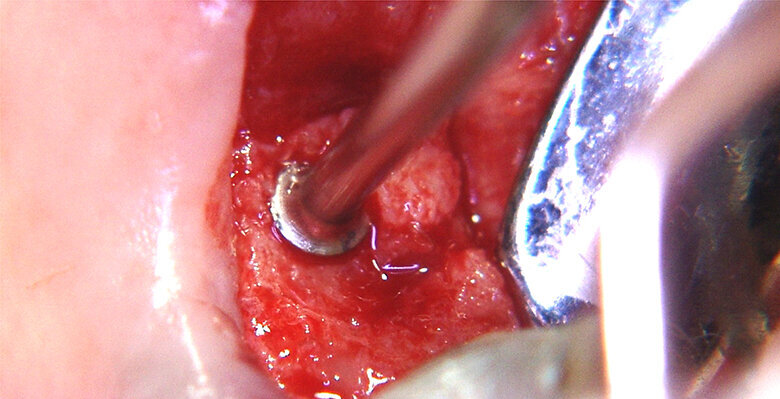

Figure 1 shows a split-mouth case with a bilateral INTRALIFT procedure: after a small crestal “booklet”-flap of approx. 7x7mm is detached, the sinus floor is safely opened with ultrasound Piezotome tips (Figs. 2 & 3), the sinus membrane then detached by the hydrodynamic cavitation effect of the Piezotome-tip TKW5 plugged into the approach canal (Figs. 4 & 5) and the subantral scaffold filled with 2cm of randomly assigned biomaterial (Figs. 6 & 7), followed by wound closure (Fig. 8). After a mean healing period of 8,4 months X-Mind trium CBCT scans were performed, the digital setup of the future bridge constructed with the AIS 3D app and the bone density determined in the sinus-lift site around a virtual implant (Fig. 9). Standardised implants (4mm in diameter and 12mm in length) were then inserted in the position of the virtual implant and insertion torque values (ITV) measured intra-surgically (test groups; Fig. 10). A total of 27 patients with sufficient native subantral crestal bone (min. crest width: 6 mm, height: 12 mm) were screened by X-Mind trium CBCT for bone density with the virtual implant (Fig. 11), the standardised implant inserted and the ITV recorded (control group). Figure 12 depicts the final result after implant insertion in the patient case shown in Figures 1–9.